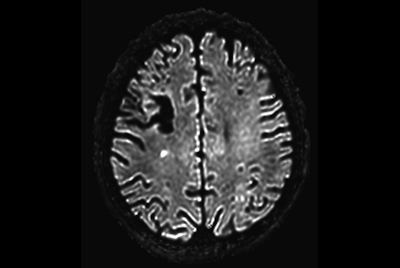

Brain infarction